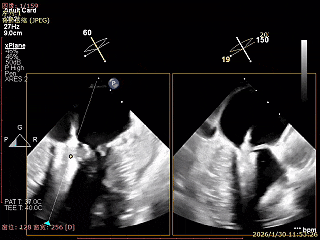

LVOT切面可见主瓣二尖瓣术后反流基本消失

植入两枚夹子后二尖瓣平均跨瓣压差2mmHg